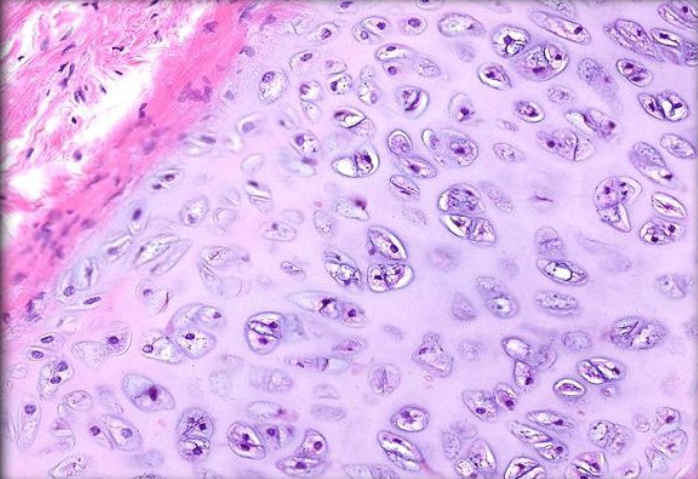

Transitional epithelium

A type of epithelium that can stretch and change shape, found in the urinary bladder and ureters, playing a crucial role in holding and accommodating urine.

<p>A type of epithelium that can stretch and change shape, found in the urinary bladder and ureters, playing a crucial role in holding and accommodating urine. </p>